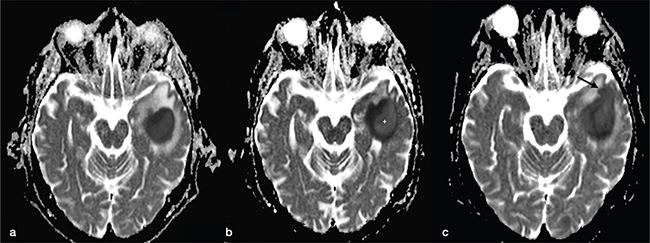

Pyogenic BAs are typically hyperintense on DWI, with low ADC values. This finding is due to the restricted motion of water in the BA cavity that contains pus: inflammatory cells, bacteria, necrotic tissue and a proteinaceous exudate with a very high viscosity and cellularity (Figure 4 and Figures 7-9).11 ADC values may have a wide range due to the different compositions of the abscess cavity, the different types of bacteria involved and the immune response of the host.12,13 Changes in ADC values on post-treatment follow-up MRI may be observed. Increasing ADC values in the abscess cavity are an early indicator of successful treatment (Figure 10). These changes in ADC values can be observed before the size reduction of the BA.12 Conversely, persistently low ADC values could represent an ineffective drug therapy, and recurrence of low ADC values might suggest active disease (Figure 9).14 DWI is also useful in improving the diagnosis of an intraventricular rupture of the BA with subsequent ventriculitis.

FIG 9. Longitudinal Follow-Up MRI Studies of a Pyogenic Abscess in a 54-Year-Old Alcoholic Man Admitted to the ER with Epileptic Seizures. Blood cultures were positive for methicillin-sensitive Staphylococcus aureus. (a) On the first brain MRI, the left temporal lesion showed marked restricted diffusion with low signal intensity on the ADC map, typical for a pyogenic abscess. (b) After 2 weeks of antibiotic therapy (oxacillin: 2 g six times a day) a new MRI was performed. No change in lesion size was observed but increased signal in the central-lateral portion of the core of the abscess on the ADC map was noticed (asterisk) suggestive of good therapy response. (c) Unfortunately, follow-up MRI performed after two more weeks of antibiotic therapy revealed signs of disease progression with an increase in size, satellite lesion (arrow in c), almost unchanged ADC values and more perilesional vasogenic oedema.